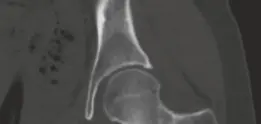

التصوير المقطعي المحوسب (CT Scan):

- يُعد التصوير المقطعي المحوسب (CT) هو الفحص الذهبي لتأكيد تشخيص الورم العظمي العظمي. فهو يُظهر بوضوح "العش" الصغير الكثيف (nidus) الذي يميز الورم، بالإضافة إلى منطقة التصلب العظمي المحيطة به.

(ملاحظة: الصورة المرفقة هي CT، ولكن الوصف يشير إلى MRI. سأستخدم الصورة المتاحة وأذكر أن MRI يظهر الوذمة).